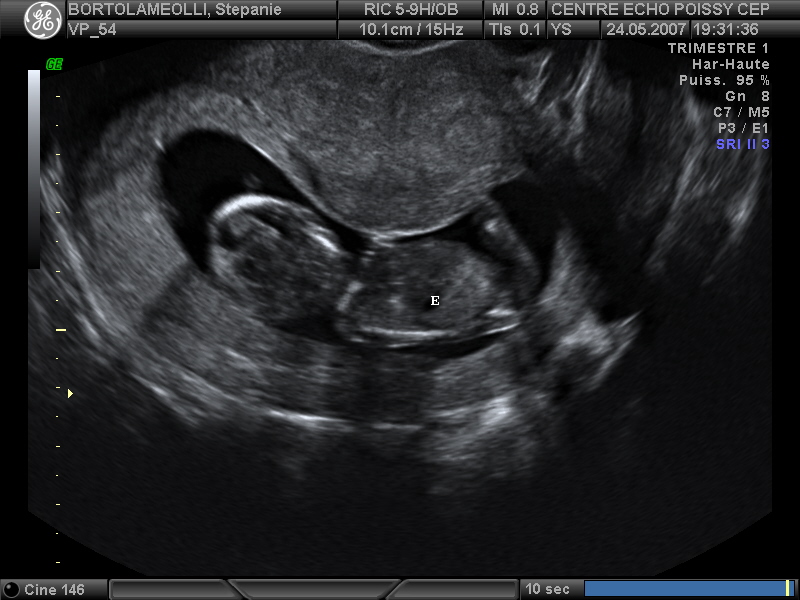

Echographies

Mai 2007